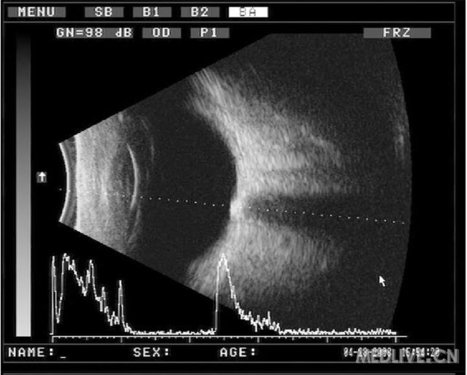

B超下影像较为典型,可见视盘处高强回声光斑,边界可;回声较强可遮挡衰减其后组织部分回声。

而视乳头水肿,视神经炎超声可见视盘处隆起,低强回声,边界不清,可以鉴别。